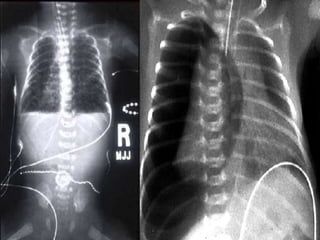

CXR   

Management Most significant discriminatoryfindings are the onset of the illness and the degree of distress exhibited by the infant Symptoms can last from a few hours to two days TTN is a clinical diagnosis CXR   